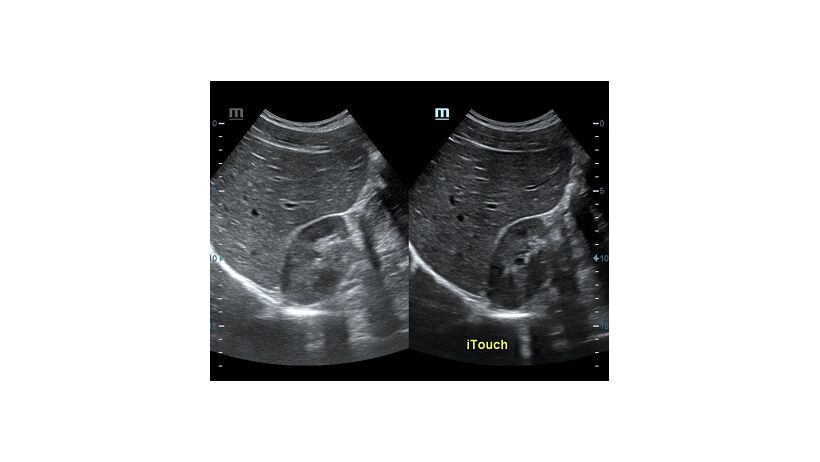

Обзор функции УЗИ: iTouch - автоматическая оптимизация изображения

Оптимизация изображения происходит и за счет постобработки. Наиболее часто используемый инструмент - общее усиление (Gain). Усиление делает изображение «ярче», но чем сильнее усиление, тем меньше различия между структурами. Также используются усиление по времени (TGC) и усиление по длине (LGC), которые позволяют изменять отображение на экране послойно, позволяя подсветить гипоэхогенные участки, или, наоборот, снизить визуально эхогенность слишком ярких моментов. Данный вид оптимизации требует много времени, для упрощения работы доктора на приборах Mindray внедрена система автоматической оптимизации - iTouch.